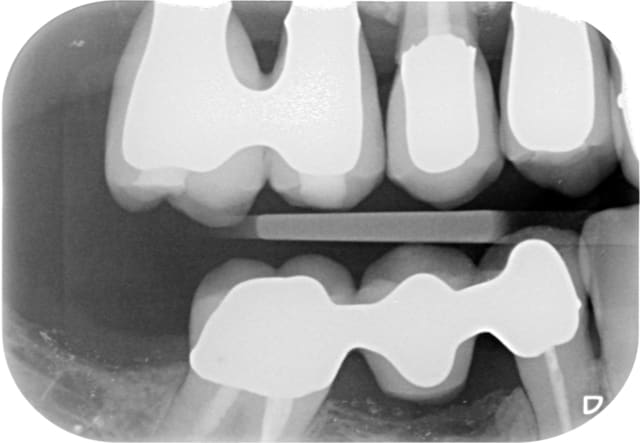

On voit bien sur l'historique radio que la migration apicale a débuté entre janvier et mai 2014. Date à laquelle j'ai dû changer la 14.

J'aime bien les points de contacts assez serrés et là j'ai le souvenir qu'il était très costaud.

Je pense donc que la migration est dû a une compression de la 15 par effet de coin comme la supputer Shadow.

De toute manière maintenant elle ne bougera plus!